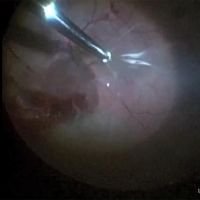

Retinal Detachment Surgery: Tips and Tricks Part 1

Mariano Iros, Tomás Castro Feijóo, Ahmed Sallam, Abdallah Ellabban, Frank Becquet, Juan Francois Le Rouic -